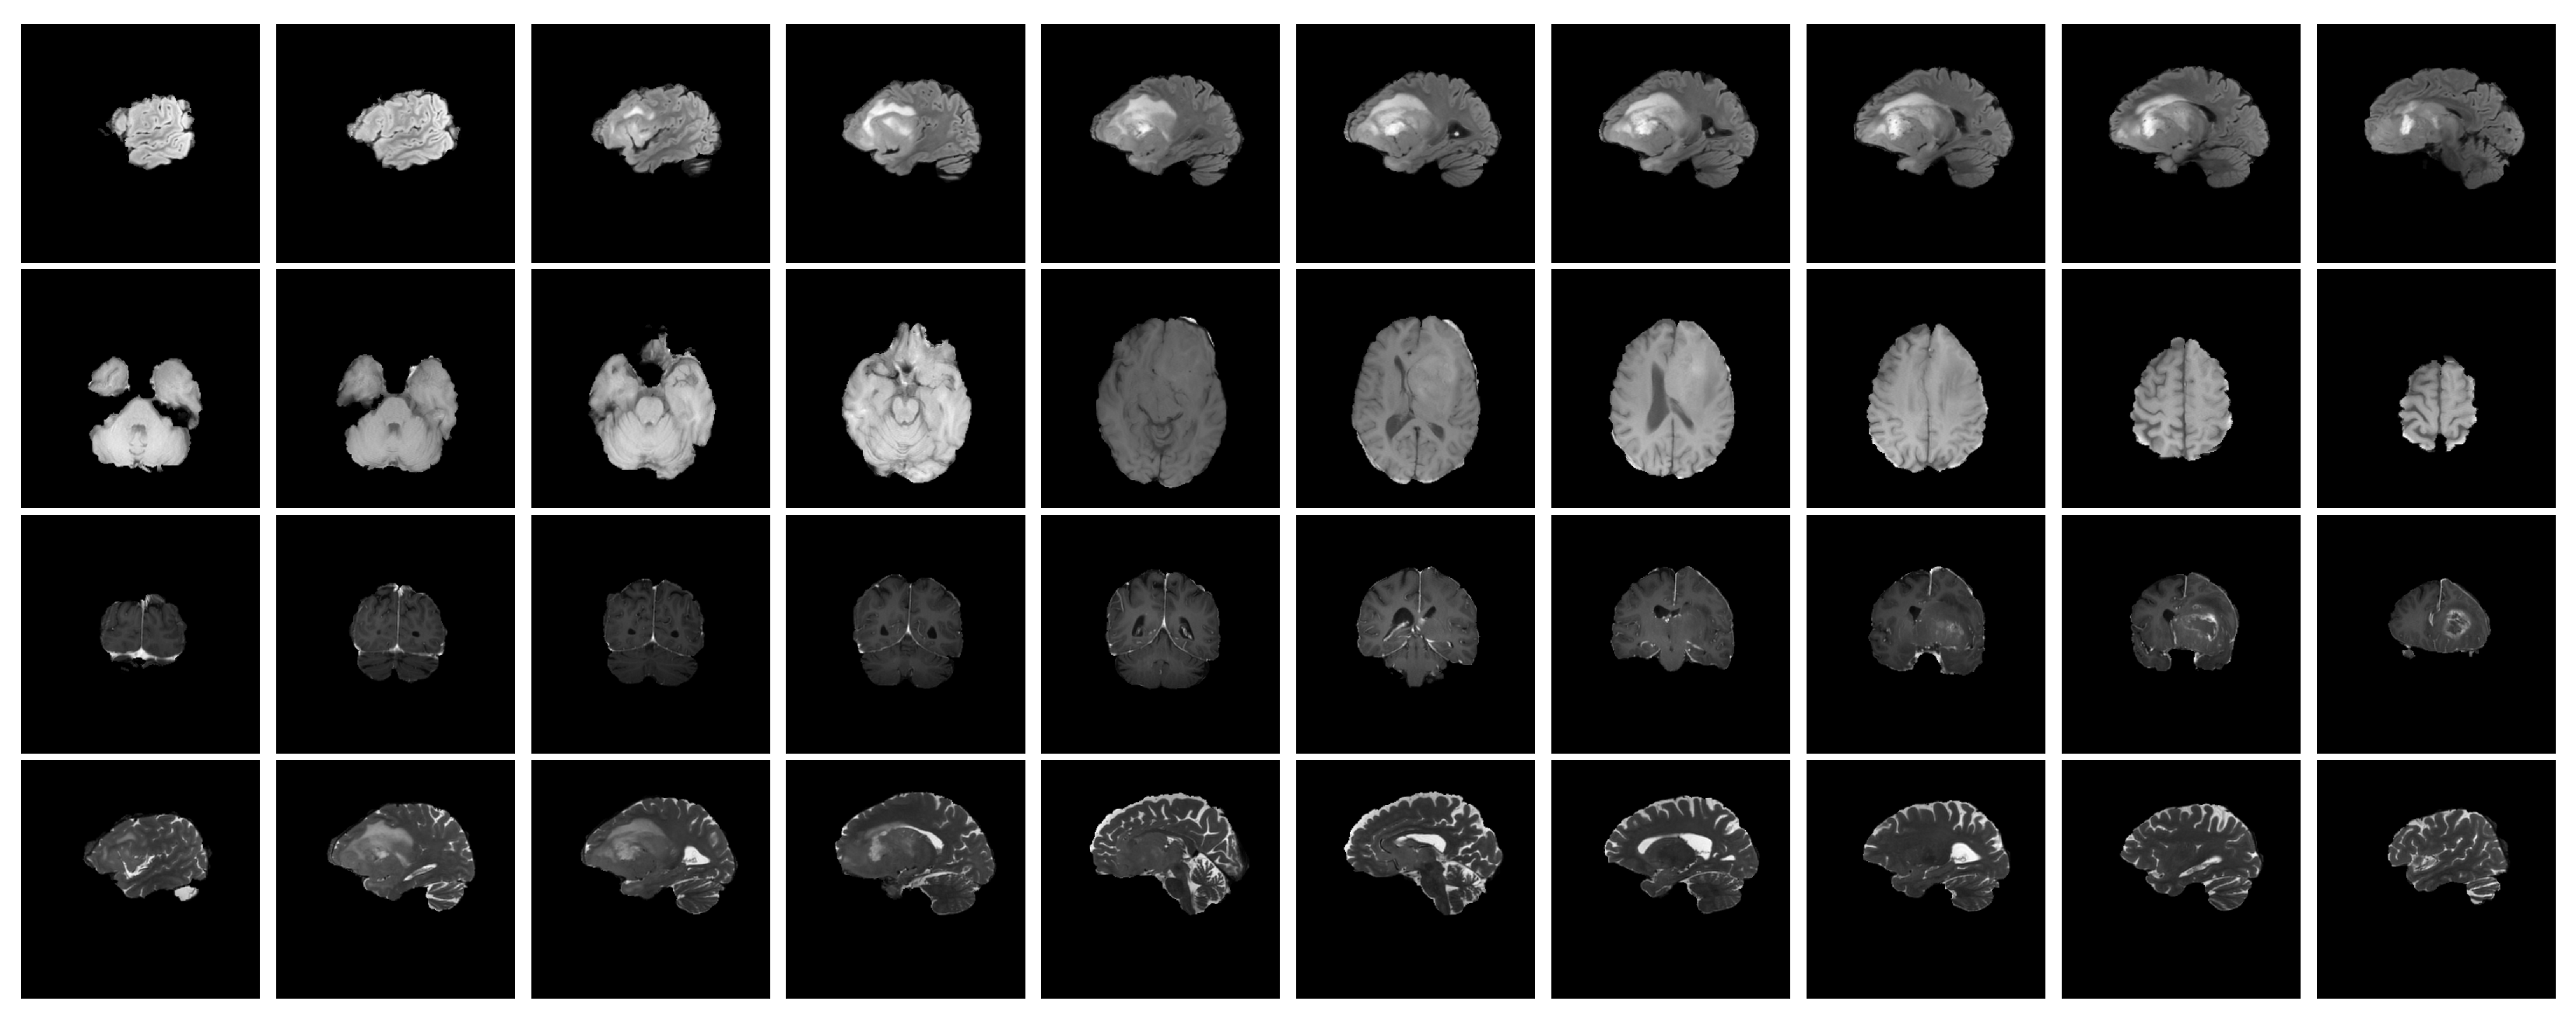

2. Related Works

3.2. Dataset

3.3. Pre-Processing